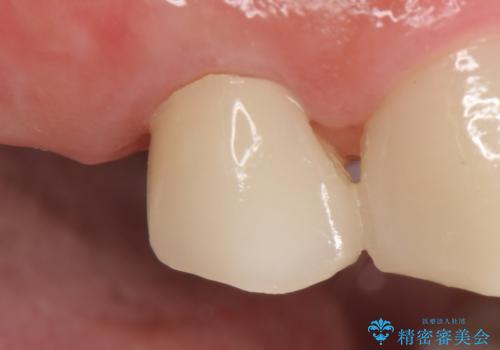

- オールセラミッククラウン…¥100,000費用は治療当時の料金となります

今回用いたオールセラミッククラウンはジルコニアフレームという白い素材の上にセラミックを盛っているため、審美性が非常に高いのが特徴です。

また、ジルコニアは人工ダイヤモンドの材料にも使われているほど高い強度を持っており、そのためオールセラミッククラウンは審美性だけでなく、奥歯やブリッジの補綴も可能とするクラウンです。